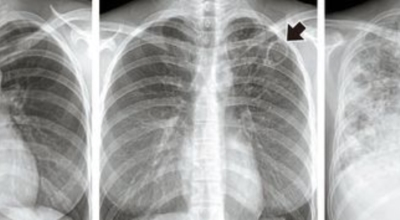

흉부 엑스레이

엑스레이 검사 방법으로는 실제 크기로 촬영하는 흉부 직접 촬영과 마이너스 70mm, 100mm 사진으로 촬영하는 간접 촬영이 있다고 하며, 일부 사람을 단체로 검사할 때 간접 촬영이 많이 활용돼요. 조사결과에 근거하면 결핵은 과감염성 결핵과 재활성성 결핵으로 구분되며, 기존 결핵은 소아결핵과 성인결핵으로 소속되는 경우가 많았어요. 인간면역결핍바이러스(HIV)에 감염된 사람들은 주로 과감염된 결핵을 보이 다고 알려져 있답니다.